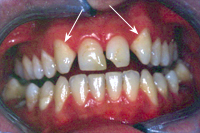

In der gleichen Sitzung hat sie dem Patienten auch die Oberkieferfront verschönert. Wegen eines genetisch angeborenen Defekts fehlen die seitlichen Schneidezähne; neben den mittleren Schneidezähnen folgen also direkt die spitzigen Eckzähne, wie in Abb. 3 gezeigt. Durch Ansetzen von Kompostifüllungen dank adhäsiver Technik wurden die Eckzähne formlich - ohne geringstes Beschleifen - zu natürlichen, seitlichen Schneidezähnen ummodelliert. Wie Abb. 4 zeigt, wurde dadurch der Schneidekantenverlauf viel harmonischer.